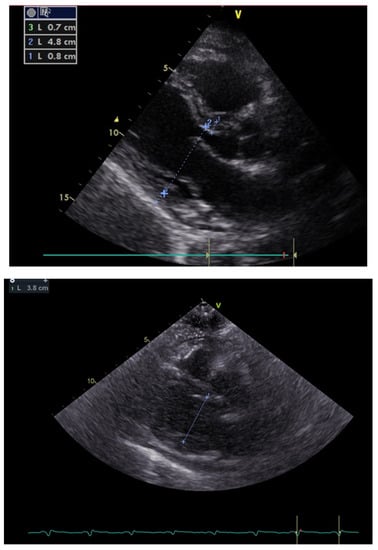

In the screening echocardiography, large pericardial effusion with signs of compression was observed, raising suspicion of cardiac tamponade (Figure 2). In addition to echocardiographic findings, the chest CT showed right-sided pleural effusion (Figure 3). A diagnosis of septic shock with multiple organ dysfunction and hypoxemic respiratory failure was made and the patient was admitted to the intensive care unit. Empiric antibiotic treatment with meropenem and vancomycin was initiated. Abdominal and pelvic CT did not show any abnormalities. Alongside the treatment for septic shock and respiratory failure, pericardiocentesis was performed and a pericardial drainage catheter was placed. About 700 mL of thick purulent fluid was drained over two days (Figure 4).

Figure 2. Transthoracic echocardiogram showing a large pericardial effusion (most prominent around the left ventricular posterior wall and the left ventricular apex with about 2.7 cm and 2.4 cm in diameter, respectively) with a ventricular systolic collapse and a ‘’swinging heart’’ view.

At the end of the second week, the patient was diagnosed with Cl. difficile enterocolitis and was treated with oral metronidazole (500 mg every eight hours) and vancomycin (250 mg every six hours) for 12 days. Subsequently, he developed dyspnea, ascites, peripheral edema, and hypotension. Echocardiography revealed pericardial constriction, compression of both ventricles, a respiration-related intraventricular septal shift towards the left ventricle, marked respiratory variation in mitral and tricuspid inflow velocities (mitral Doppler velocity with an inspiratory decrease of 27% and tricuspid Doppler velocity with an increase of 33%), and an increase in the hepatic vein expiratory diastolic reversal flow (Figure 5).

Figure 5. Markedly decreased left ventricular diastolic diameter from long axis parasternal view within 20 days.